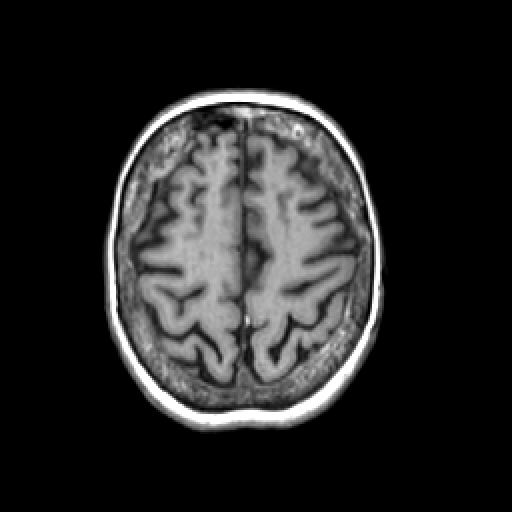

T1-weighted structural MR: Slice 41

Slice 41